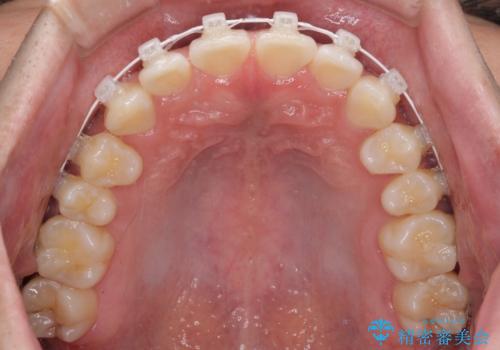

- 矯正装置

- 審美装置

- 1年1ヶ月

- 10-30回